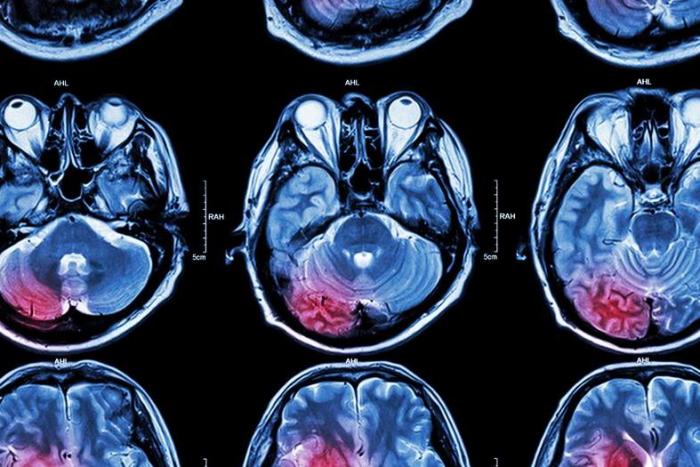

Gracias a varias décadas de investigaciones dedicadas a las bases biológicas de las enfermedades mentales, se han logrado considerables progresos en el conocimiento del funcionamiento del cerebro y se han podido proponer hipótesis muy interesantes respecto a la fisiopatología de dichas enfermedades.

- Resonancia magnética